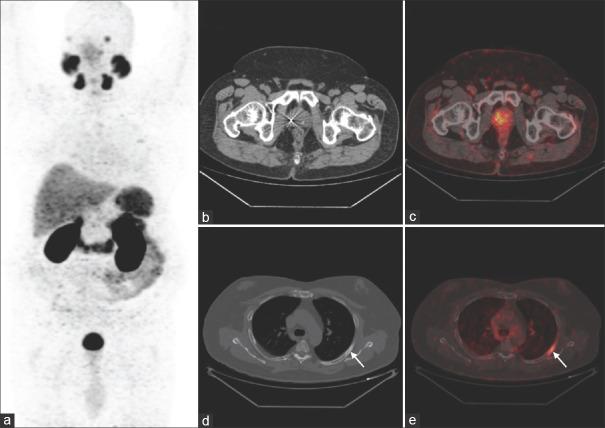

The study included 170 men, all had adenocarcinoma of the prostate, 124/170 had previous RP and 46/170 had prior RT. The median serum PSA in the RP group was 1.8 ng/ml and 5.2 ng/ml in the RT group. In the post-RP cohort, the detection rate of Ga PSMA PET/CT was 39.3% for PSA 0.2 to <0.5 ng/ml, 47.3% for PSA 0.5 to <1 ng/ml, 68.4% for PSA 1 to <2 ng/ml and 93.1% for PSA ≥2 ng/ml. In the post-RT group, the detection rate was 88.8% for PSA 2 to <4 ng/ml and 100% for PSA ≥4 ng/ml.

该研究纳入了170名男性,均为前列腺腺癌,其中124/170曾接受过RP,46/170曾接受过RT。RP组血清PSA中位数为1.8 ng/ml,RT组为5.2 ng/ml。在RP后队列中,PSA 0.2至<0.5 ng/ml时Ga PSMA PET/CT的检出率为39.3%,PSA 0.5至<1 ng/ml时为47.3%,PSA 1至<2 ng/ml时为68.4%,PSA≥2 ng/ml时为93.1%。在RT后组中,PSA 2至<4 ng/ml时检出率为88.8%,PSA≥4 ng/ml时为100%。